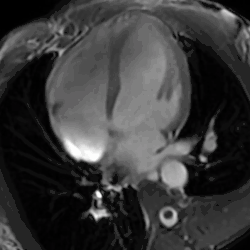

4 chamber cine view of a healthy male athlete's heart, demonstrating dramatic enlargement of all chambers (LVOT at 69mm) and thickening of the heart walls.